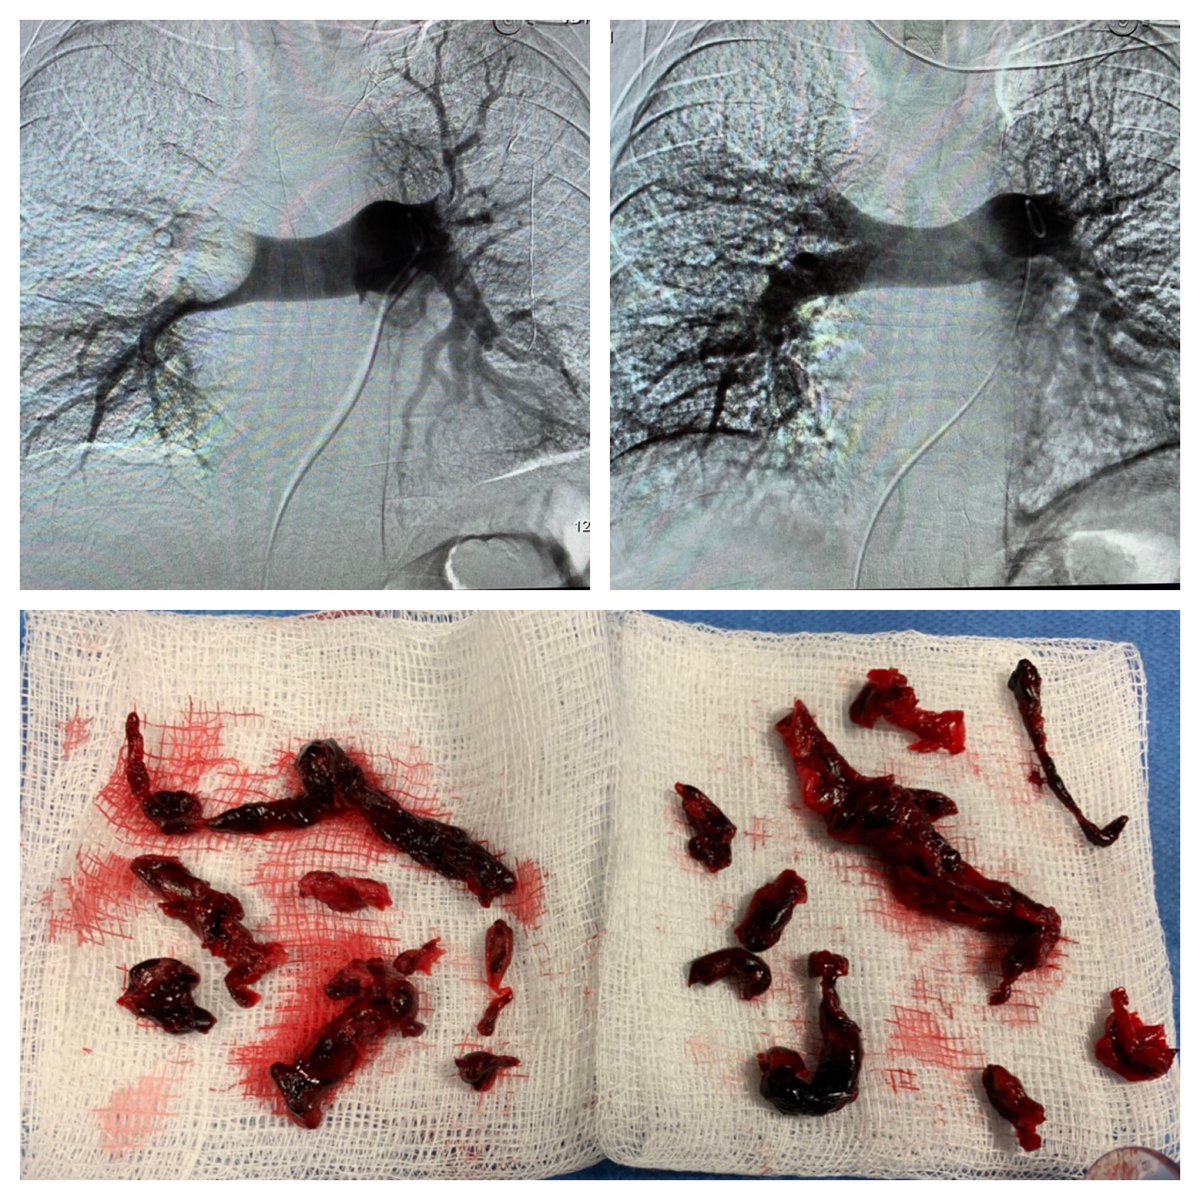

47 yo p/w massive PE s/p systemic tPA and persistent hypotension. Extensive right-sided PE on angio. Thrombus completely removed with FlowTriever mechanical thrombectomy. PA pressure decreased to 30mmHg from 64 mmHg immediately. #IRad @SIRspecialists @SIRRFS @SIR_ECS @JVIRmedia